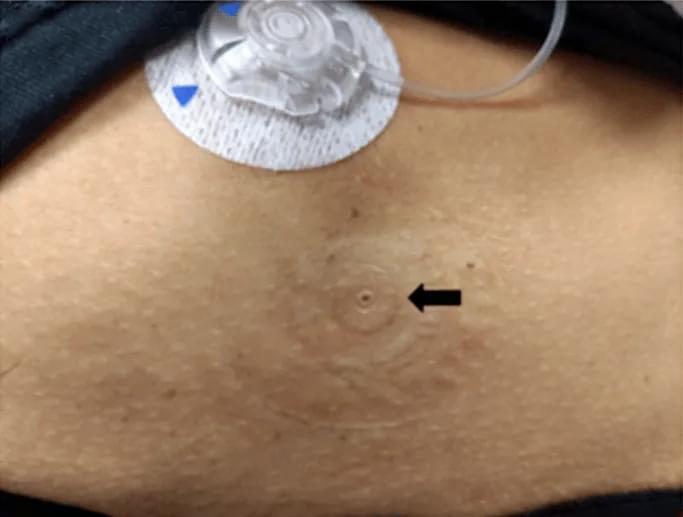

3、一般每48~72小时更换输注部位,每次更换后原输注部位可外用抗菌药膏或全身应用抗生素。

另外,患者每天应检查输注部位2次以上。查看是否有红肿、出血及针头套管脱出,如出现上述现象,应立即更换储液管、输注装置及输注部位。有皮肤病者治愈后才能装泵。